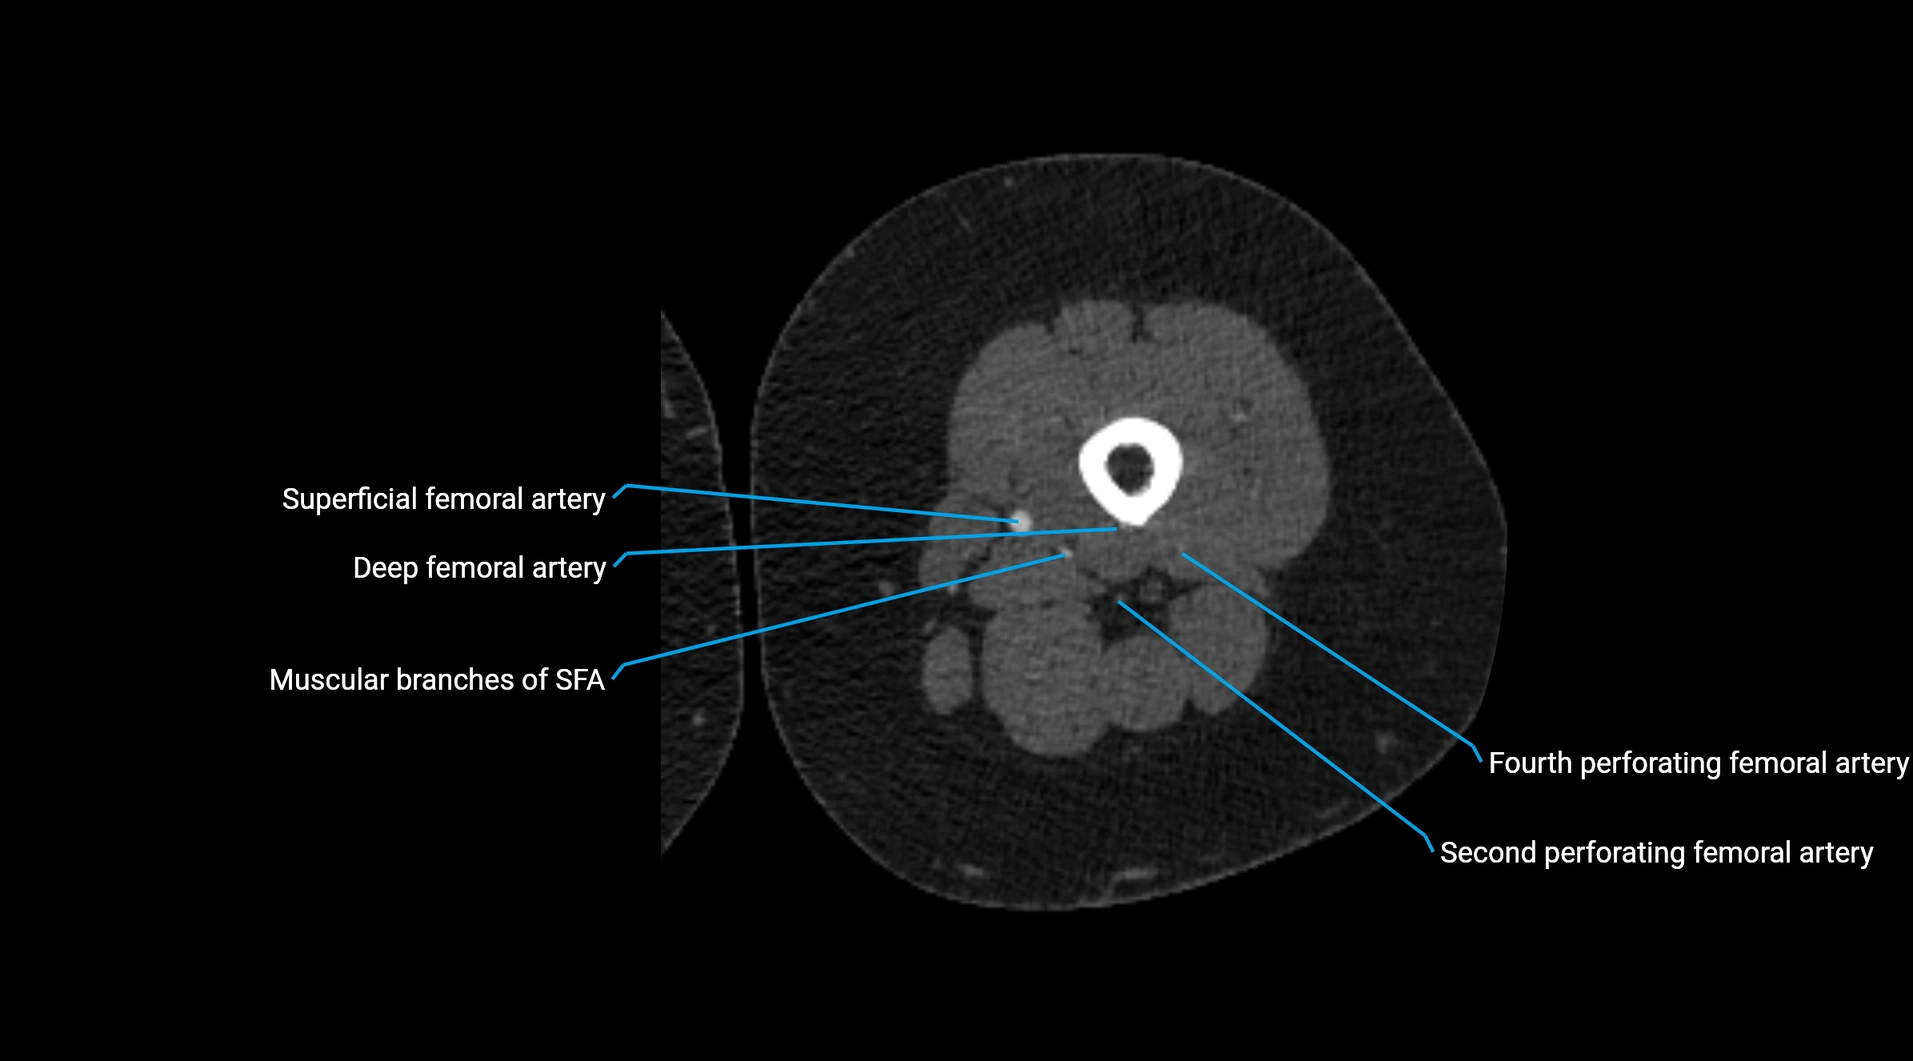

CT Appearance

Non-contrast CT:

• Appears as a tubular soft tissue structure anterior to vertebral bodies

• Calcified atherosclerotic plaques appear as hyperdense foci along the wall

• Useful for screening abdominal aortic aneurysm (AAA) size and mural calcification

Contrast-enhanced CT (CTA):

• Gold standard for abdominal aortic imaging

• Provides excellent detail of lumen, wall, aneurysm, thrombus, and branch vessels

• Multiplanar and 3D reconstructions help in aneurysm measurement, stent graft planning, and dissection evaluation

• Detects acute rupture, traumatic injury, or occlusion with high sensitivity